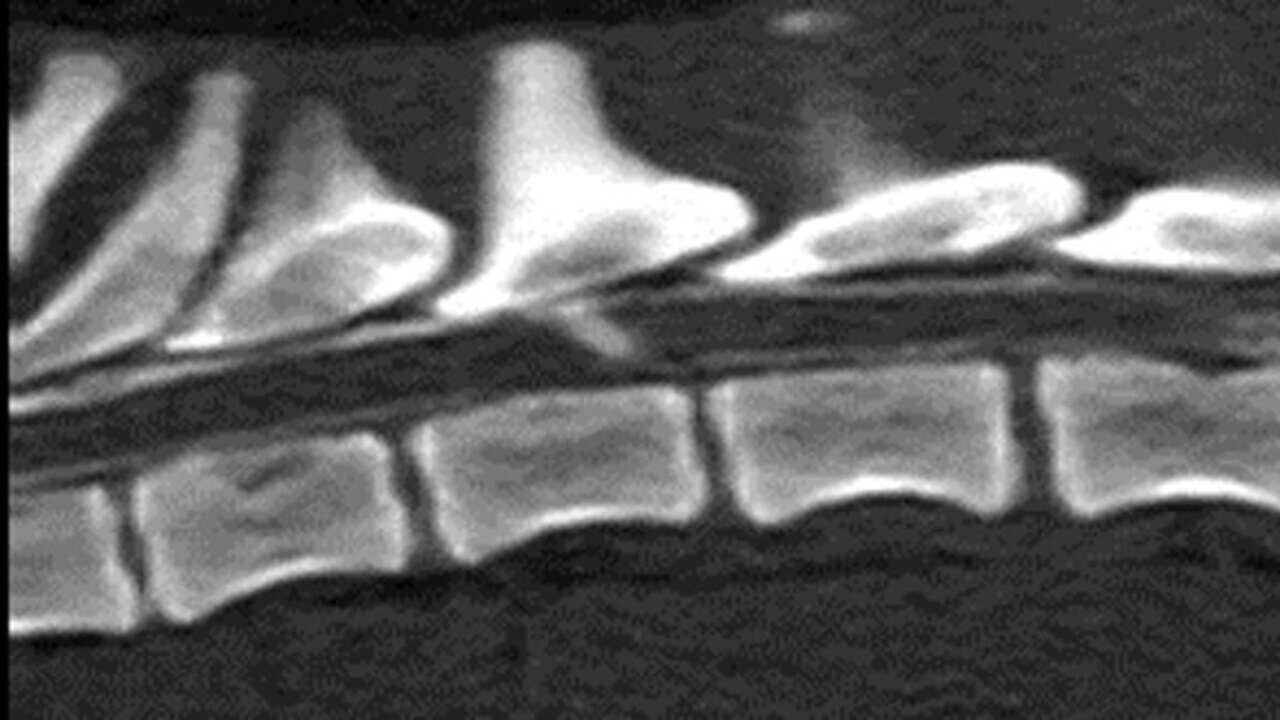

Se realizó la anestesia general el mismo día para el estudio radiológico con radiografías de la columna toracolumbar en dos proyecciones, mielografía y mielo-TAC:

- Las radiografías mostraron una reducción del espacio intervertebral T12-T13 y la mielografía descartó mielopatías compresivas.

- En el mielo-TAC, en la reconstrucción sagital, se observó un trayecto lineal de contraste en dirección ventrodorsal desde el espacio intervertebral T12-T13 hasta el aspecto dorsal del parénquima medular a nivel de T12.

- Además, se observó acúmulo de contraste intramedular a ese mismo nivel con cierta atenuación de la línea ventral de contraste (imágenes 2A y 2B).

Imagen 2. Caso 1. A) Reconstrucción sagital en ventana de hueso del mielo-TAC en la que se observa el trayecto de contraste en dirección ventrodorsal desde el espacio T12-T13 hasta el aspecto dorsal del parénquima medular a nivel de T12. Se aprecia estrechamiento del espacio T12-T13 y atenuación del contraste ventralmente a ese mismo nivel. B) Imagen transversal del mielo-TAC, adquirida en algoritmo de hueso a nivel de T12 del mielo-TAC, en la que se puede ver el acúmulo de contraste intramedular y su trayecto.